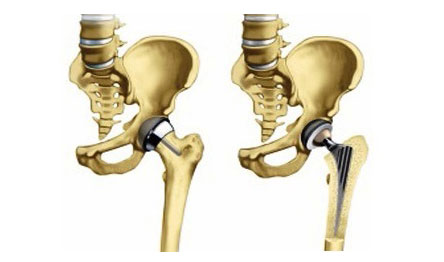

На третій стадії захворювання хірургічне втручання стає єдино можливим способом боротьби з коксартрозом. Якщо на кістках тазостегнового суглоба збереглася достатня кількість хряща, застосовується такий різновид операції, як артропластика. В ході втручання відбувається моделювання суглобових поверхонь, видалення їх деформованих фрагментів.

Ендопротезування призначається, коли зберегти суглоб можливості немає. Головки однієї або обох кісток замінюються пластикової або металевою конструкцією.

Операція триває близько 2-3 годин. Загальний період реабілітації - 2 місяці після виписки.

Прогноз після операції сприятливий. Протези високої якості можуть служити до 20 років.